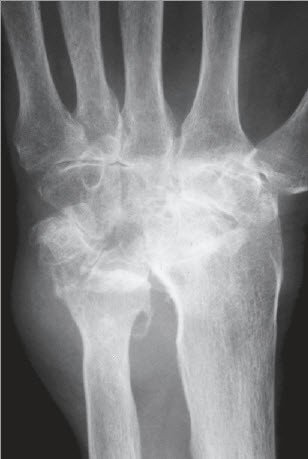

Eine Verdachtsdiagnose kann bereits durch die Patientenbefragung und das aktuelle Beschwerdebild gestellt werden. Gesichert wird die Diagnose einer Arthrose dann durch ein Röntgenbild. Findet sich nur eine leichte Arthrose, müssen möglicherweise Zusatzuntersuchungen durchgeführt werden. Bei fortgeschrittenen Arthrosen mit Gelenkzerstörung findet sich im Röntgenbild nur noch ein schmaler oder auch gänzlich fehlender Gelenkspalt (Abb. 1a bis 1c).